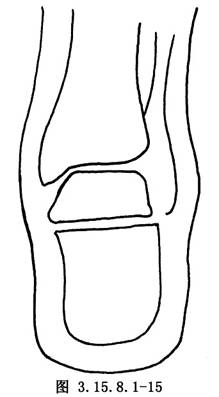

先用骨刀截除跟骰关节和距舟关节,楔形截骨基底在背外侧纠正内翻畸形(图3.15.8.1-8),切除角度等于X线片第2趾和足中线形成的角度(图3.15.8.1-9)。若纠正足外翻畸形,楔形截骨基底可设计在内侧(图3.15.8.1-10),由于距舟关节和跟骰关节在一个平面上,切除角度是一致的(图3.15.8.1-11)。最后切除距下关节,纠正跟骨内收(图3.15.8.1-12),根据X线片胫骨中线和跟骨中线形成的角度,做外侧楔形切除(图3.15.8.1-13)。当骨刀切到对侧时,注意轻缓,尤其纠正外翻时,更要注意防止误伤胫后的血管及神经(图3.15.8.1-14)。将已切除的骨面合拢,如畸形纠正,骨面能紧密对合(图3.15.8.1-15),周围空隙植入切除多余的松质骨。